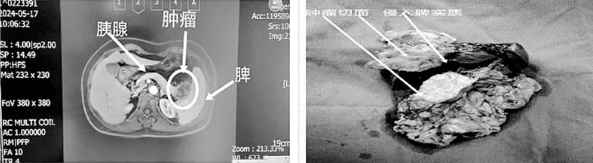

近日,红河州第三人民医院﹒红河州肿瘤医院肝胆外科在徐耀端主任的带领下,率先在州内完成第一例“单孔腹腔镜下胰腺体尾部癌联合脾脏根治性切除术”,术后患者手术切口愈合良好(甲级愈合),无严重并发症发生,术后住院5天康复出院。

该院肝胆外科徐耀端主任介绍:胰腺癌是一种主要起源于胰腺导管上皮及腺泡细胞的恶性肿瘤,恶性程度极高,起病隐匿,早期诊断困难,进展迅速,生存时间短,是预后最差的恶性肿瘤之一,被称为“癌中之王”,其发病率和死亡率都高居全球和我国恶性肿瘤的前10位。传统胰腺癌切除手术主要为开腹或多孔腹腔镜方式,本次红河州第三人民医院﹒红河州肿瘤医院率先在州内采用“经脐单孔腹腔镜”的方式进行手术。相较于传统术式,“经脐单孔腹腔镜”具有手术切口小、术后疼痛轻及恢复迅速的特点,是目前国内较新且较少医院掌握的手术方式,但该手术操作难度及对手术医师的要求均高于传统术式。该院肝胆外科作为红河州肿瘤医院下设的专业诊治肝脏恶性肿瘤、胆囊恶性肿瘤、胆道恶性肿瘤、胰腺及十二指肠恶性肿瘤的专科科室,始终以不断加强专业领域内疾病理论学习及诊治能力为抓手,积极学习国内外先进诊疗方法及经验,努力服务和保障人民群众身体健康。